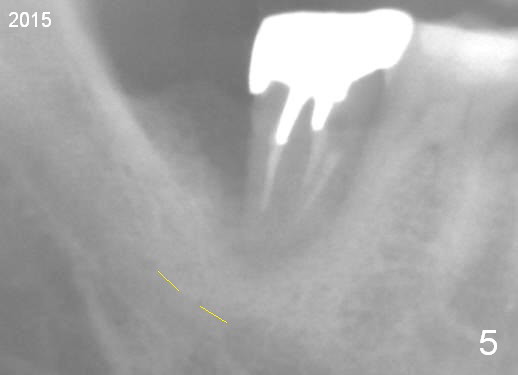

A 44-year-old man has had an asymptomatic distal defect of the tooth #31 for 8 years (Fig.1-5). Recently there is an acute episode of swelling and pain. A fistula develops mesiobucally. Panoramic X-ray films tend to show that the distal defect is deep (Fig.2,5; yellow dashed line: upper border of the Inferior Alveolar Canal). In addition, the distal defect may be not even buccolingually, as indicated by white and red arrowheads in Fig.3,4. Following placement of a 6.9x10 mm bone-level implant, a 7.8x4 (4.5) mm cemented abutment is inserted for try in (Fig.6). When it is fit, it is removed and a cover screw is temporarily placed. A piece of Osteotape (~10x4 mm) is placed distobuccally or distolingually (depending upon which wall is lower). A small amount of bone graft is packed between the most coronal portion of the implant and the Osteotape. The cover screw is then removed and the abutment is re-inserted and tightened by hand. An immediate provisional is fabricated with well-trimmed margin. Reline is done if necessary for securely holding bone graft in place. A new PA is to be taken prior to surgery to determine the extent of the lesion. Photos are taken to show the mesiobuccal fistula. Return to Lower Molar Immediate Implant Xin Wei, DDS, PhD, MS 1st edition 04/12/2015, last revision 05/25/2018